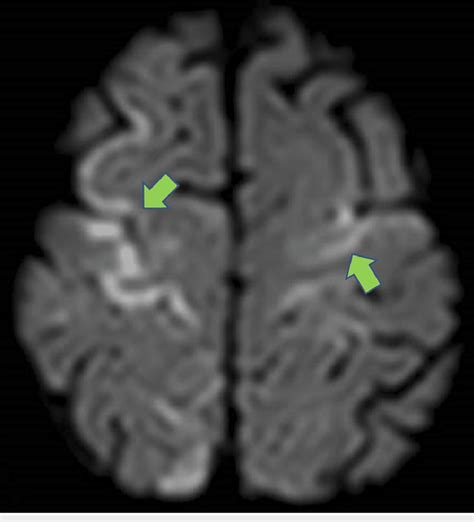

Interpreting Diffusion-Weighted Imaging (DWI) scans can seem a bit daunting at first, but once you understand the basic principles, it becomes much clearer. The most critical thing to remember is that restricted diffusion appears bright on DWI images . Why bright? Because the sequence is designed to attenuate the signal when water diffuses freely, and preserve the signal when diffusion is restricted. So, areas where water molecules can’t move easily – due to swollen cells, tightly packed structures, or other microstructural changes – will stand out as hyperintense, or bright, spots. The most classic example is an acute ischemic stroke . In the early minutes to hours after a stroke, brain cells become damaged, their cell membranes lose integrity, and water rushes in, causing them to swell. This swelling severely restricts the movement of water molecules. Consequently, the affected area lights up brightly on the DWI scan. This is often the very first sign of a stroke visible on MRI. However, it’s crucial to distinguish true restricted diffusion from other phenomena that can also cause bright signals. One important consideration is T2 shine-through . Some tissues naturally have a long T2 relaxation time, meaning they appear bright on conventional T2-weighted images. If these tissues also have some degree of diffusion, their signal might still appear bright on DWI, even if diffusion isn’t truly restricted. This is where the ADC map comes in as your best friend. Remember, the ADC quantifies the actual rate of water diffusion, independent of T2 effects. In areas of true restricted diffusion (like a stroke), the ADC values will be low . In contrast, areas that are bright on DWI due to T2 shine-through will have normal or even high ADC values. So, the combination of a bright DWI signal and a corresponding low ADC value is the hallmark of restricted diffusion and strongly suggests a pathological process like stroke or cytotoxic edema. Another important interpretation point is anisotropy . In tissues like the white matter of the brain, water diffusion isn’t the same in all directions. It tends to follow the direction of the nerve fibers. Multi-directional DWI and ADC tensor imaging can reveal these directional differences, which are crucial for understanding the integrity of white matter tracts. For instance, conditions that damage these tracts, like multiple sclerosis or TBI, can alter the pattern of diffusion. In tumors, DWI can help assess cellularity. Highly cellular tumors often exhibit restricted diffusion (bright on DWI, low ADC), which can help differentiate them from less cellular tumors or other lesions. So, when you’re looking at a DWI scan, always look at the DWI image and the ADC map together. The DWI highlights potential areas of concern, and the ADC map helps confirm whether the signal change is due to true diffusion restriction or something else. It’s this combined interpretation that makes DWI such a powerful diagnostic tool.